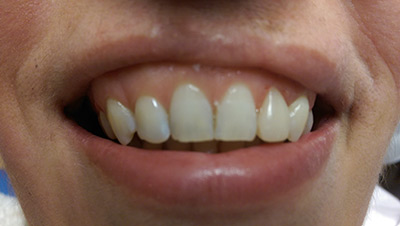

Fogmegtartó kezelések

Amennyiben pácienseink rendszeresen részt vesznek az éves szűrővizsgálaton, az esetek jelentős részében elkerülhetőek a foghúzások, szájsebészeti komolyabb beavatkozások, és csupán apróbb kezelésekre lehet szükség! Ilyenek például a szájhigiéniás kezelések, esztétikus tömések, betétek, koronák, gyökérkezelések.

Betegeink többféle (kémiai kötésű és fényre kötő) esztétikus tömés közül orvosainkkal együtt választják ki a megfelelőbbet! Fémmentes betéteinkkel, koronáinkkal természethűen tudjuk visszaállítani fogazatát. Gyökérkezeléseket csúcstechnológiás gépi tágítóval végezzük, aminek segítségével milliméter pontosan tudjuk bemérni a gyökértöméshez a csatorna hosszát.